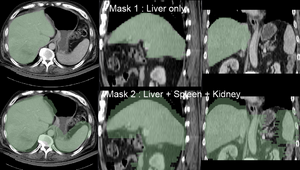

Note: for illustration the example set contains 2 masks: one with only the liver and one also including spleen and kidney (Mask2). As shown in the results below, the liver-only mask is insufficiently constraining the registration, yielding a result that at first glance looks ok for the liver, but has significant misalignment in the remaining abdominal area. Hence it is advisable to stabilize the registration further by including more structures with good contrast in both images (Spleen, Kidney).

3. using the Brush tool, trace the liver contour from axial slices. Also include kidneys and spleen.

4. repeat the same for the CT.

5. you should end up with 2 label maps similar to those included in the example dataset. See snapshots in Result section below.

registration masks